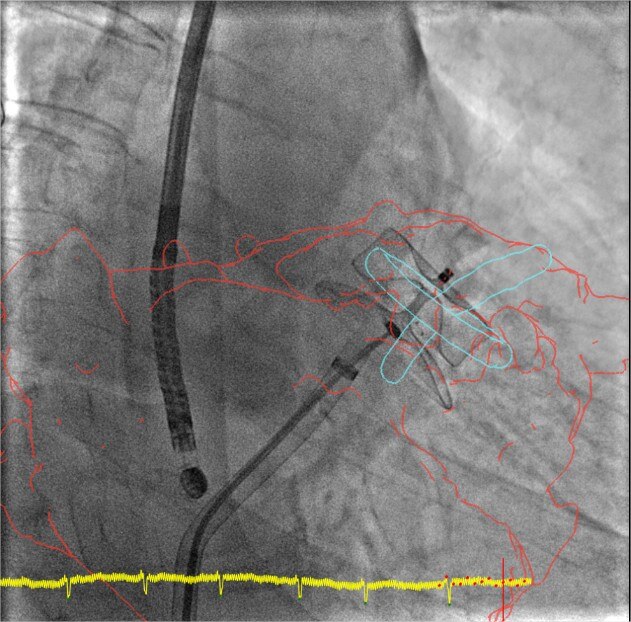

product-product-categories-Interventional - 2016-valve_12.jpgFührung

Die um die Funktion Calcification Enhancement (Kalzifizierungshervorhebung) erweiterte 3D-Fusionsführung sorgt für eine verbesserte Darstellung bewegter Strukturen mit Kontrast.